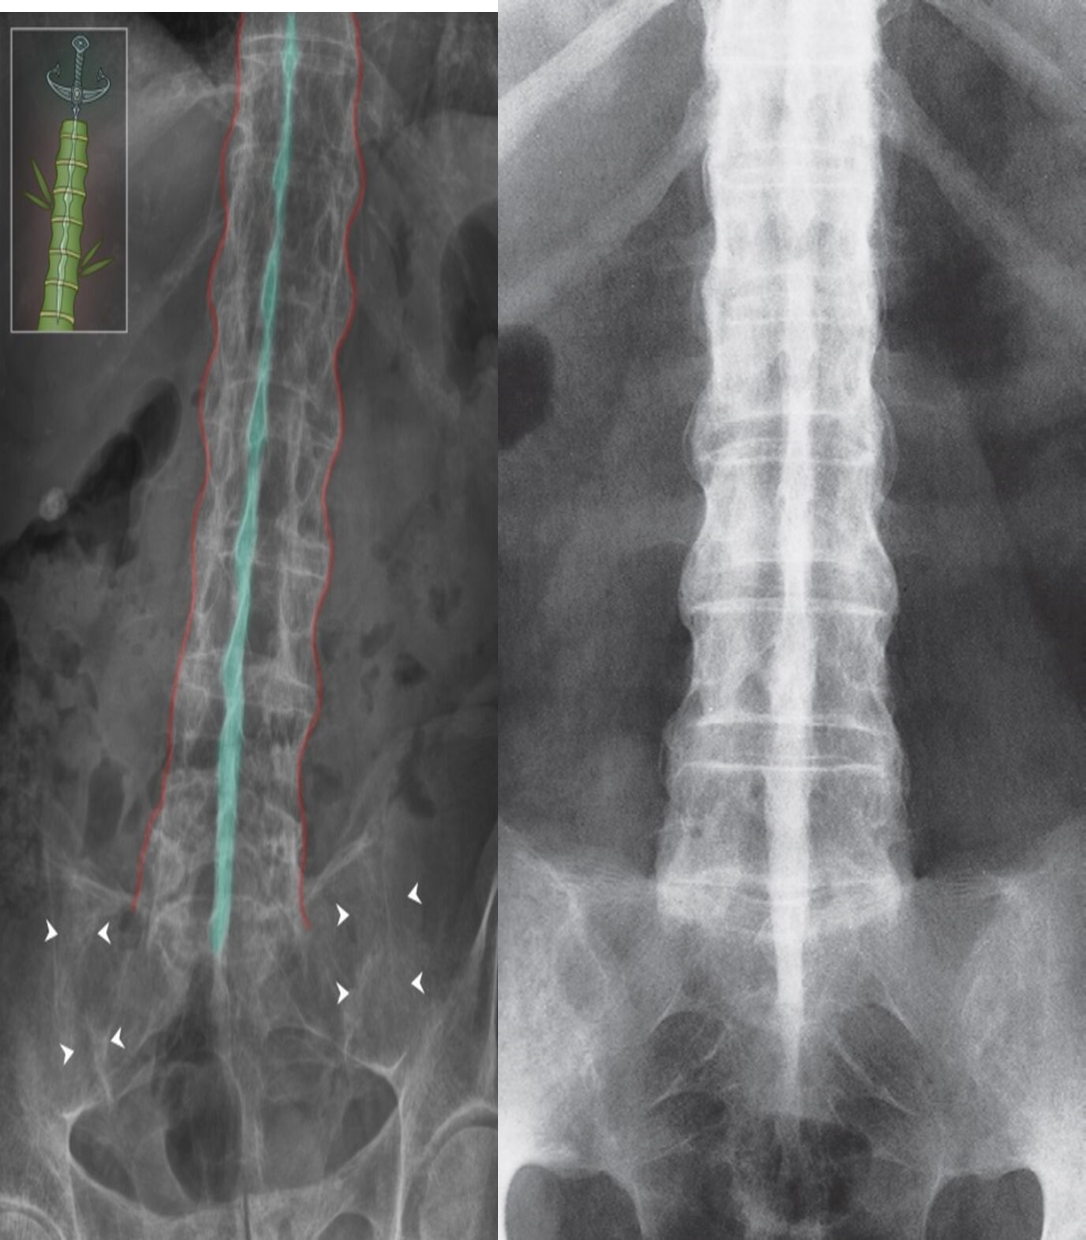

- Dagger sign: A radiodense line running through the center of vertebral bodies on AP view Caused by ossification of vertebral ligaments

- Bamboo spine: seen in later stages and is caused by the following Ossification of outer fibers of the annulus fibrosus resulting in ankylosis (fusion) of intervertebral joints

Bamboo spine

Bamboo spine and dagger sign in ankylosing spondylitis

X-ray lumbar spine (AP view)

Marginal syndesmophytes formed by ossification of outer fibers of the annulus fibrosis have caused the spine to resemble a bamboo stem (so-called “bamboo spine”;.

Additional ossification of supraspinous and interspinous ligaments has produced a dense line (dagger sign; green overlay) projecting through the vertebrae. Fusion (ankylosis) across the sacroiliac joints (indicated by arrowheads) can also be seen.